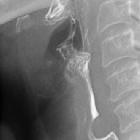

Prominentes

pharyngoösophagealen Segment bei gastroösophagealem Reflux. Unterhalb des nicht ganz geöffneten Sphinkters zeigt sich dorsal auch Luft im Sinne eines Jetphänomens.

Ein prominentes pharyngo-ösophageales Segment, also die Betonung der cricopharyngealen Kontraktion am Ende der Schluckphase, oder auch eine inkomplette Öffnung des oberen Ösophagussphinkters sind indirekte Hinweise auf einen gastroösophagealen Reflux. Sie werden als Schutzreaktion des oberen Sphinkterapparates gegen eine Aspiration bei saurem Ösophagusinhalt gedeutet.